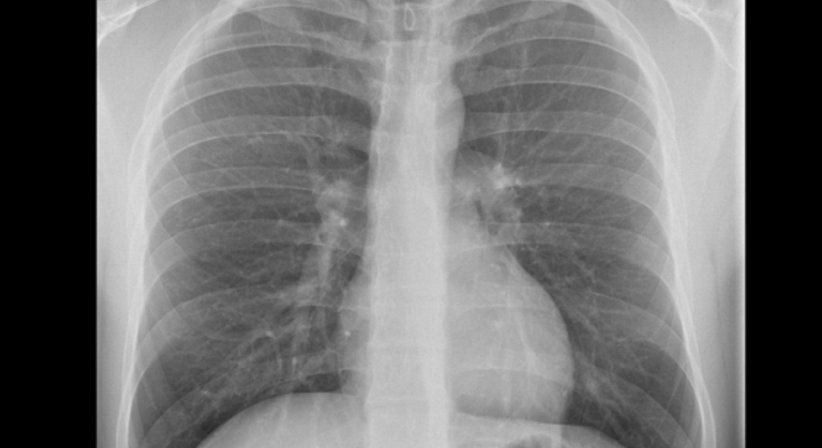

Bei Röntgenstrahlen handelt es sich um energiereiche elektromagnetische Wellen, die in der Lage sind den Körper zu durchdringen und die Organe dadurch abbilden können. Es entsteht dabei keine radioaktive Strahlung.

Röntgenstrahlen sind besonders zur Unters​uchung von Lunge und Knochen geeignet. Mit zusätzlich verabreichten Kontrastmittekönnen auch auch Magen, Darm, Nieren und Gefäße gut dargestellt werden.